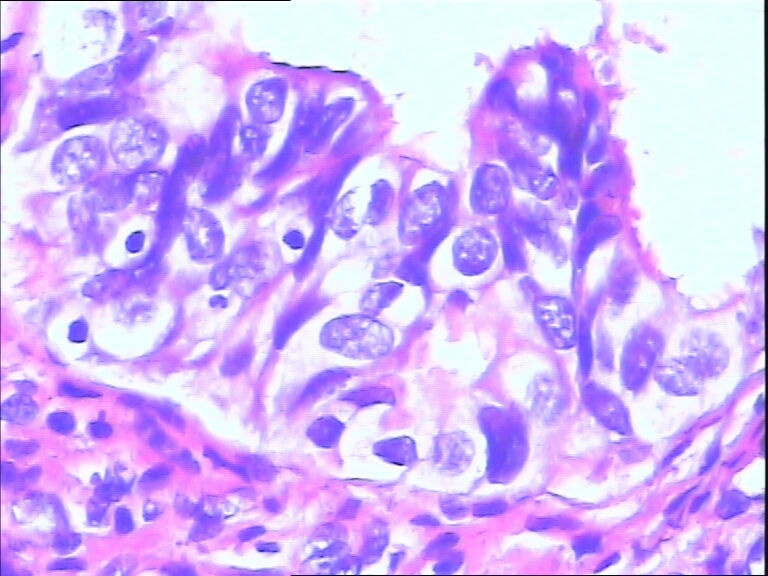

女,43y

左输卵管积液

输卵管长4.5cm;直径:0.8cm

• 请教:输卵管!图3

图3

输卵管增生性上皮病变。

慢性炎伴上皮增生

良性,炎症改变

考虑炎症